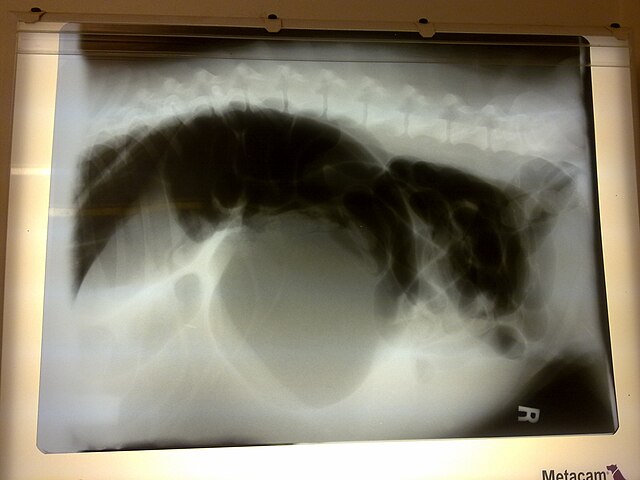

Case Study #42 • GIT Surgery

Gastric Volvulus (GDV)

Master the emergency flow. From decompressing the stomach to the final gastropexy decision.

X-Ray Indicators